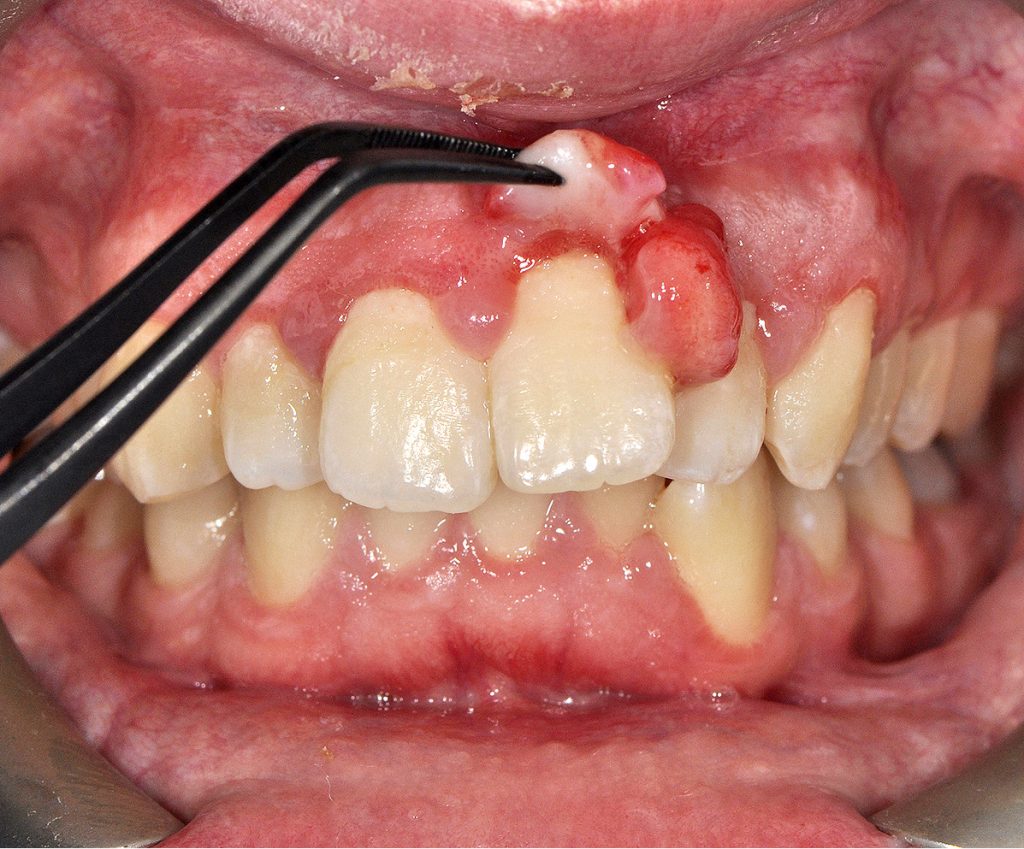

- Opis przypadku: mężczyzna, lat 22, zgłosił się do gabinetu stomatologicznego z powodu zmiany egzofitycznej na dziąśle wyrostka zębodołowego przedniego odcinka szczęki.

Streszczenie: W pracy przedstawiono opis przypadku chirurgicznego leczenia nadziąślaka zapalnego u 22-letniego pacjenta. Zmianę rozrostową usunięto w całości po fazie wstępnej niechirurgicznego leczenia periodontologicznego. Badanie histopatologiczne potwierdziło rozpoznanie kliniczne – granuloma pyogenicum. Leczenie przyczynowe wraz z instruktażem higieny w pierwszym etapie leczenia, całkowite usunięcie zmiany z marginesem tkanek zdrowych w fazie chirurgicznej oraz edukacja i motywacja pacjenta w fazie podtrzymującej pozwoliły uniknąć wznowy w 6-miesięcznym okresie obserwacji.

Summary: The paper is a case report describing the treatment of a 22-year-old male patient with inflammatory epulis. The proliferative lesion was completely removed after a nonsurgical phase of the periodontal treatment. The histopathological examination confirmed clinical diagnosis – granuloma pyogenicum. Elimination of causative factors along with oral hygiene instructions in the initial phase of the therapy, complete excision of the lesion with a margin of healthy tissues in the surgical phase, as well as the education and motivation of the patient in the maintenance phase enabled avoiding recurrence in the 6-month follow-up period.